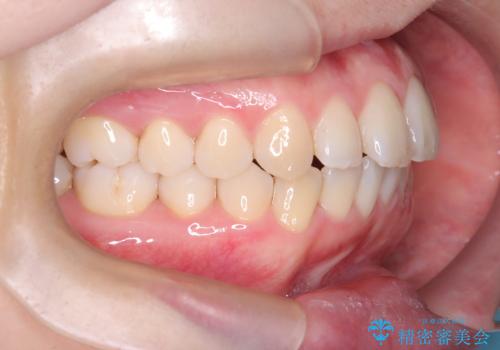

- 「前歯が出ているのが気になる」との主訴で来院されました。診察の結果、上下の前歯が前方に突出し、口元がやや目立つ印象でした。また、歯列の中心線(正中)も上下でずれており、かみ合わせのバランスにも問題がありました。

前歯の傾きが改善され、横顔の印象が大きく変化。上下の正中も一致し、かみ合わせのバランス(臼歯関係)も整いました。目立たず快適に治療ができた点にもご満足いただき、「人に気づかれずにここまで変化できるとは思わなかった」とのお声をいただいています。治療後はリテーナーを用いて、仕上がりをしっかり保っています。